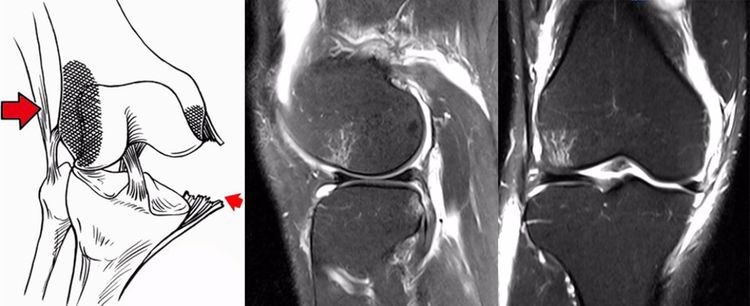

2.方向异常(ACL 下垂征):有较完整的韧带低信号,但方向异常,呈下垂状。一般见于股骨附着部的陈旧损伤,损伤的ACL下垂并粘附在PCL上。

9.jpg